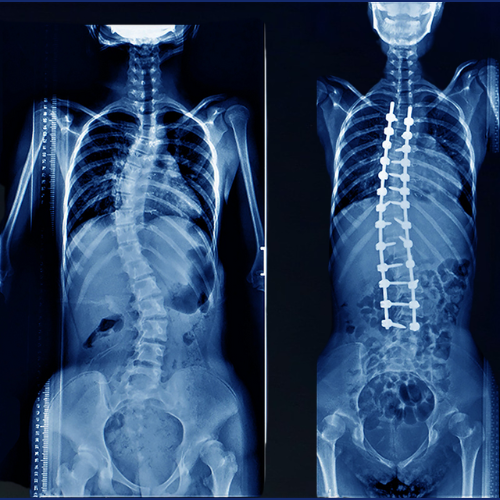

Deformity Correction

Deformity correction is a medical procedure to fix abnormally shaped, bent, or twisted bones or tissues. It restores normal alignment and function to parts of the body like the spine.

scolisis-surgery

Scoliosis Surgery

Established in vision by group of dedicated people to provide College was made medical education